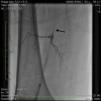

Case reportA 50-year-old Caucasian woman with hypertension, tobacco abuse, and peripheral arterial disease with life-limiting claudication had stents placed in bilateral 80% ostial iliac artery lesions two months previously. She was also noted to have a CTO of the left SFA at the ostium with no obvious stump (Figure 1) which was reconstituting distally via collaterals just above the popliteal artery (Figures 2 and 3). Due to her ongoing symptoms despite optimal medical therapy, it was decided to intervene on the SFA. Since there was no obvious stump of the occluded SFA proximally, we decided to approach the CTO through a retrograde approach.